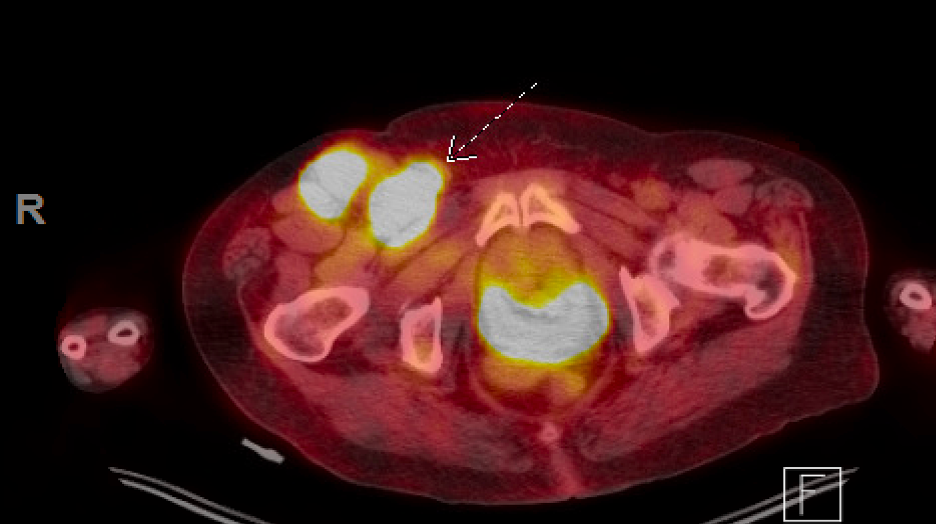

Based on the initial recommendations from podiatry and surgical oncology, ultrasound-guided fine-needle aspiration of the right inguinal lymph node took place in February 2021, which confirmed the initial suspicion of malignant melanoma. The patient received a formal diagnosis of BRAF-positive, wild type metastatic acral lentiginous melanoma of the right heel. A PET scan performed two days later, revealed a 6mm right pulmonary nodule, an 8mm subpleural nodule in the lateral right lower lobe, multiple enlarged right inguinal lymph nodes (the largest measuring 3.6x3.7cm), right external nodes all metabolically active, a large soft tissue mass at the posterior right heel measuring 4.7x4.5cm, and a small satellite cutaneous nodule at the medial right ankle.